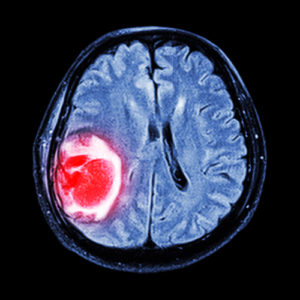

4. Tumors – Your cognitive abilities can be affected by a tumor, and more ironically its treatment. If the tumor is located in your brain, more than likely it will affect your brain’s function. The treatment for the tumor, such as chemotherapy, surgery, and radiation, can even have an effect on your memory.